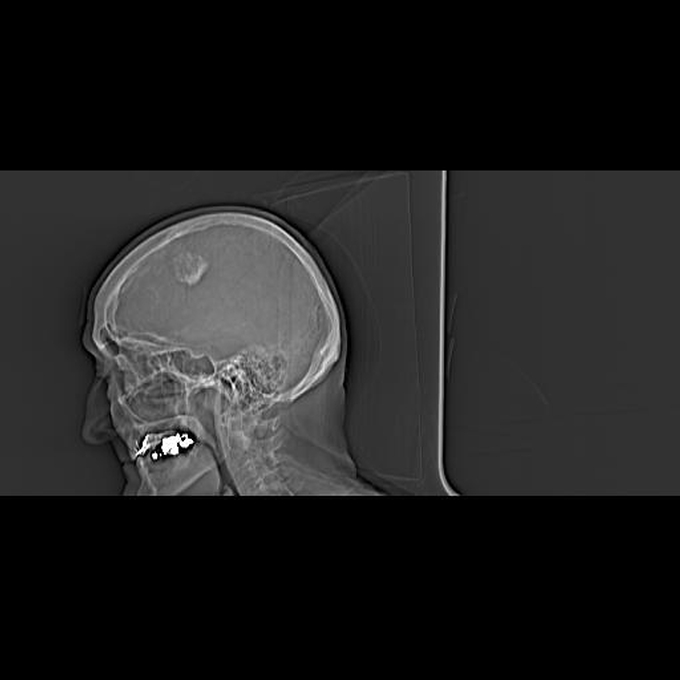

56 year old patient with dyspagia. A tumor of soft tissue was described in upper mediastinum on plain X-ray of the thorax. What is this mass in the upper mediastinum?